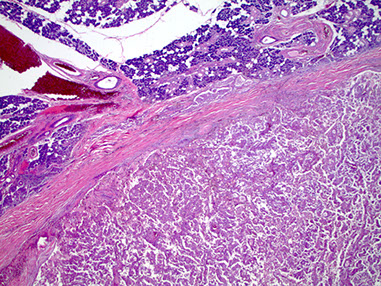

Subacute necrotizing sialadenitis of the left palate c focal acinar necrosis (stars)

Subacute necrotizing sialadentiis

Necrotizing sialometaplasia of the palate with pseudoepitheliumatous hyperplasia (PEH)